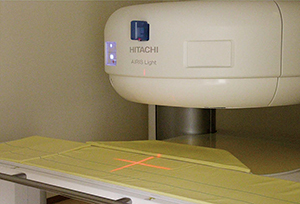

「テーブルは手動ですが,指だけで押せるほど軽く,大変扱いやすいです。撮像中心の位置がレーザーで十字に示されるため,スムーズにセッティングでき,検査準備の時間を短縮できます」

コンパクト設計のAIRIS Light |

スタッフが並んで作業することが可能な横配置テーブル |

撮像中心を示すレーザーガイド |